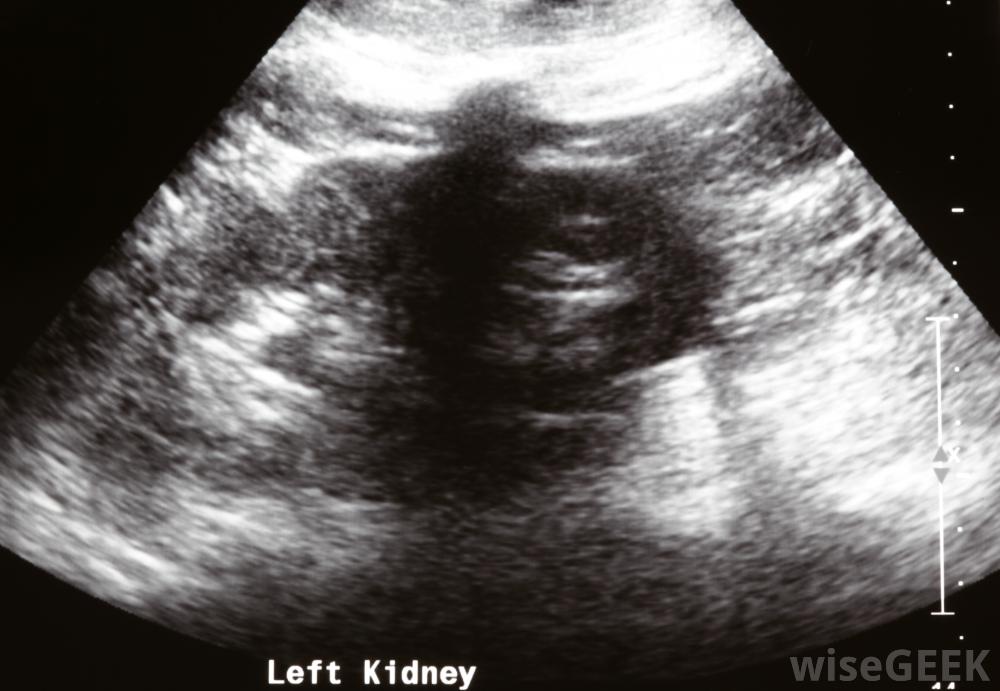

護士通常會在場監督患者生命體征,以及疼痛和焦慮程度。醫務人員,通常是放射科醫生,將使用x光或超聲波來定位腎臟。此時,一根針直接穿過皮膚的所有層插入腎臟。x射線染料通過針頭插入以幫助插入導尿管。導管被插入腎臟,有時在長時間保持原位時用針固定

在腎造口術中,超聲用于指導插管。